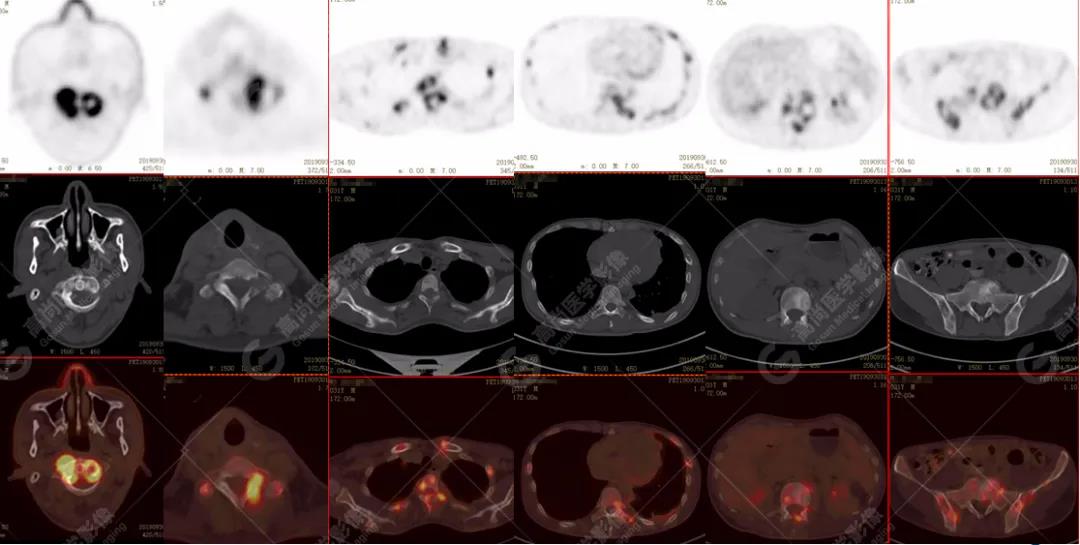

全身多發(fā)高代謝腫大淋巴結,中央代謝缺損

左肺上葉尖后段及下葉背段多發(fā)簇狀斑點狀高代謝灶

左側胸膜結節(jié)樣增厚,代謝不同程度增高

雙肺、左側胸膜多發(fā)結節(jié)影,全身多處骨質破壞,全身多發(fā)淋巴結腫大,代謝攝取不均勻性增高。

2.全身多系統(tǒng)、多形態(tài)、多發(fā)病灶(肺部、胸膜、淋巴結、骨),18F-FDG攝取不均性增高;

特征:肺部病灶簇狀分布,上葉尖段及下葉背段為著;腫大淋巴結分布不對稱,無融合、中央有壞死改變,與淋巴瘤、轉移瘤等有一定的鑒別診斷意義;